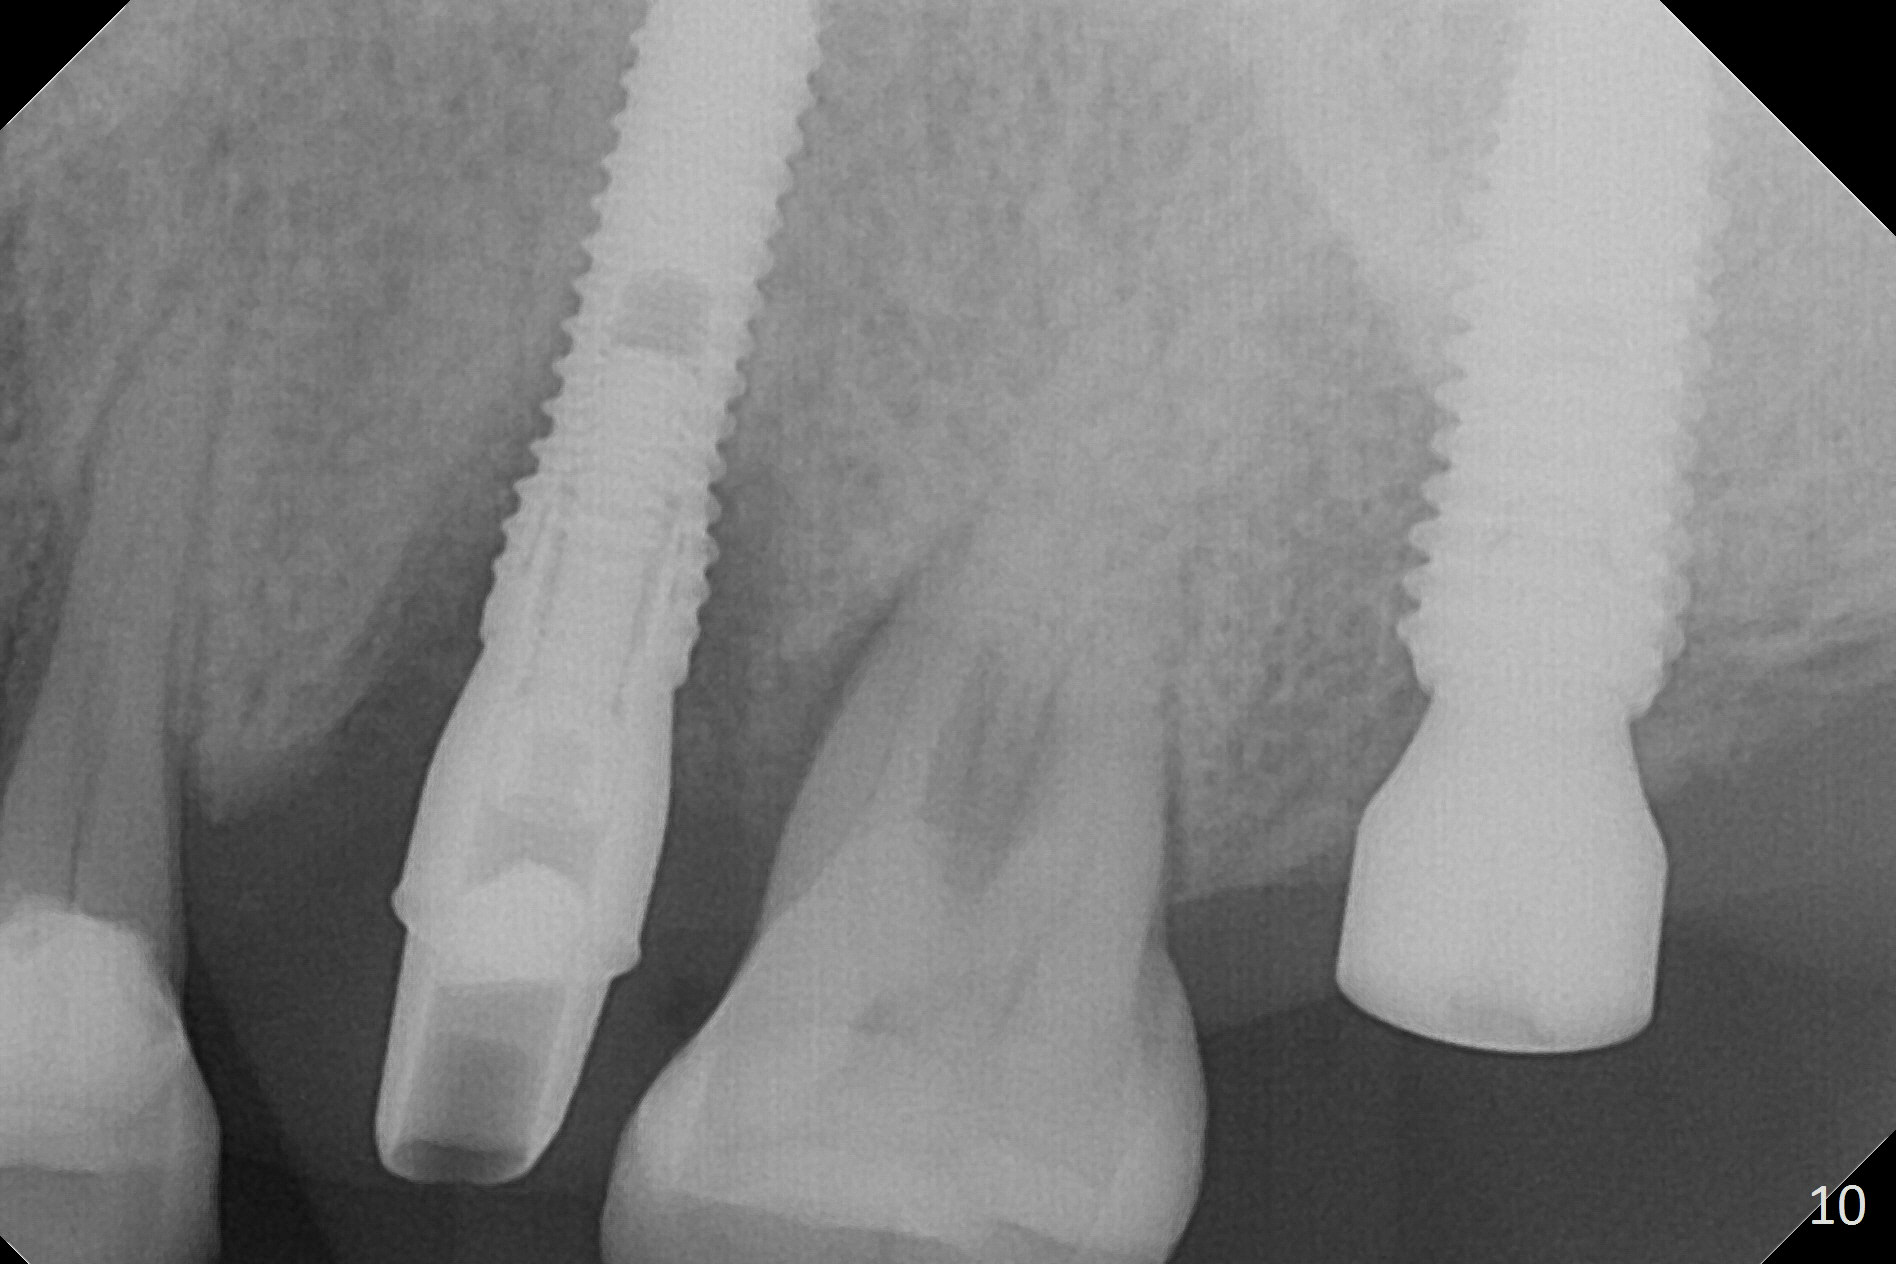

Initial osteotomy depth is 18 mm (Fig.1 green line) with 9 mm in the native bone (red line).  The bone density feels to be low.  There is at least 2 more mm bone apically (pink line).  The depth is increased by 2 mm so that when a 3.8x15 mm implant is placed, there is 10-11 mm implant/bone contact (Fig.2 red line).  There is large bony defect (Fig.3 *), which is bone grafted (Fig.4 *).  Finally a longer abutment is placed (4.5x5.5(5) in Fig.4 vs. 4.5x4(5) in Fig.2,3).  The 5 mm cuff does not look too long buccally (Fig.5) or palatally (Fig.6).   To prevent postop buccal gingival overgrowth (2), the buccal margin of an immediate provisional is subgingival (Fig.7-9 *).  Bone density between #13 and 14 appears to increase 3 months postop (Fig.10).  The implant seems to be equi-crestal (Fig.11 ^).  There seems to be more bone growth (i.e., decreasing gap) 6 months postop (Fig.12).  Impression is taken.  A crown is delivered nearly 7 months postop (08/07/2017).   While there is minimal bone loss at #13 and 15 three years and 4 months post cementation, the tooth #14 and 18 are mobile (Fig.13,14).